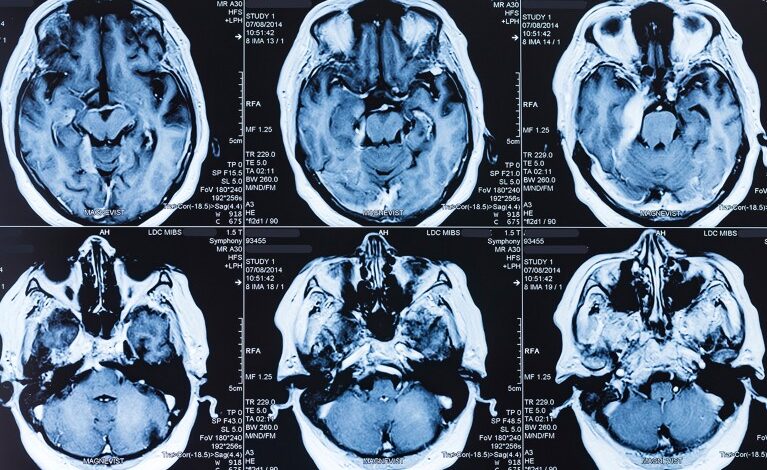

МРИ је међу револуционарним технологијама које су произашле из фундаменталне науке вођене радозналошћу.Кредит: Владимир Булгар/СПЛ

Ланчана реакција полимеразе — фундаментална наука која стоји иза ПЦР тестова који се користе за идентификацију бактерија и вируса који су постали део свакодневног живота током пандемије ЦОВИД-19 — потиче од рада на бактеријама које су у врелим изворима пронашли микробиолози Хадсон Фриз и Томас Брок са Универзитета Индијана у Блумингтону. Магнетна резонанца (МРИ) настала је из проучавања основних физичких својстава атомског језгра, а студије отровних гуштера одиграле су кључну улогу у развоју лекова као што је Оземпиц који опонашају ГЛП-1 хормон. Телевизори са равним екраном имају своје корене у студијама хемикалија које су изоловане из шаргарепе. Невс Феатуре покрива седам истакнутих примера, али постоје бројни други.